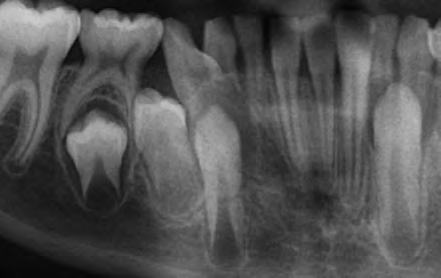

All of the patients below had been told they required extractions by orthodontists, some insisting that they could not be treated without extractions.

They were all treated without extractions, head gear or facemasks at Vakresmil and represent just a small sample of cases treated between 2004–2014.

The patient below had severe crowding of both upper canines and the lower right 5. The upper 4’s and 2’s were actually in contact.